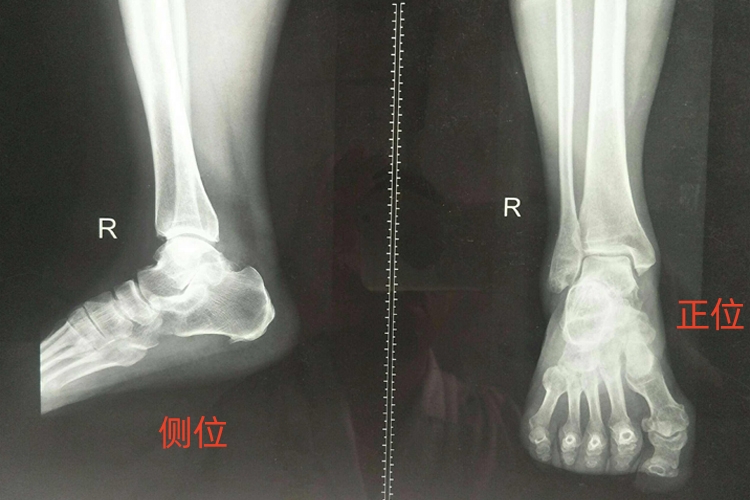

正侧位片图片

踝关节正位片

从踝关节正位片上看,关节间隙呈倒“U”形,均匀等宽,约0.5cm,内踝间隙清楚。如倒“U”形关节间隙某一部位出现不等宽,则说明此处韧带或关节囊有挛缩;如内踝间隙不清楚或变窄,则说明踩关节内翻畸形,此处软组织有挛缩。如倒“U”形关节间隙全部模糊,则可能为类风湿关节炎初期;如倒“U”形关节间隙全部变窄,则可能为类风湿关节炎晚期,关节囊全部挛缩。

踝关节侧位片

正常的踝关节侧位片,内外踝部分重叠,腓骨偏后,外踝比内踝长,胫骨后踝较大,向后突出,外形圆钝,踝骨前唇较小,微向前突,边缘锐利。关节间隙弧度向上,均匀等宽。如关节间隙宽窄不均,则表示距骨有相应程度的移位。